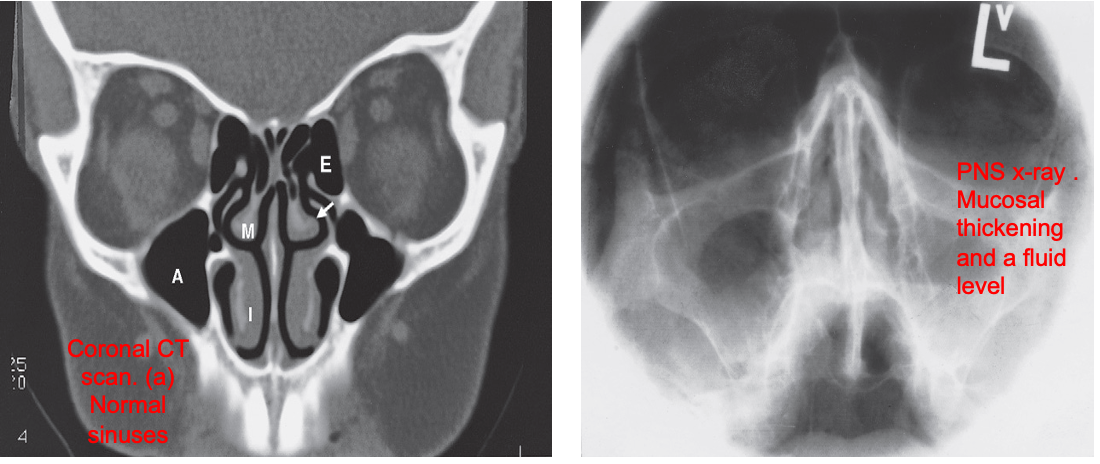

PN Sinuses

- On plain radiographs the normal sinuses are transradiant because they contain air.

- Plain films have a role in showing mucosal thickening, fluid levels and fractures.

- In most sinus disease, CT is the preferred technique.

- MRI also demonstrates the sinuses well, but is rarely required as the primary investigation